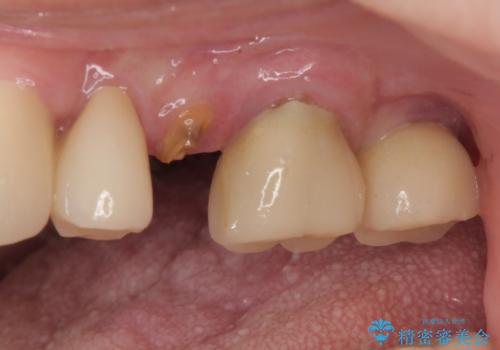

- 奥歯に装着していたクラウンが外れてしまったとのことで来院された患者様です。

診察したところ、歯根に破折線が確認され抜歯が必要な状態でした。

歯肉や歯槽骨の状態は良好であったため、抜歯即時埋入インプラントによる補綴治療を行うこととしました。